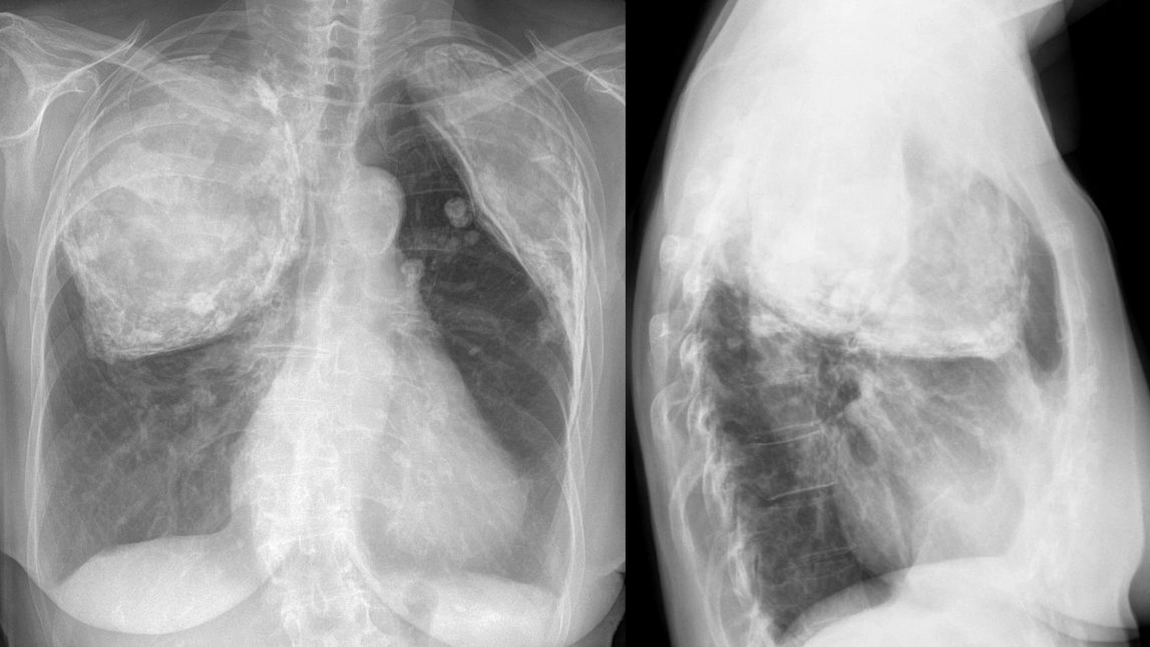

Vaccinul împotriva tuberculozei bun pentru diabetici. Un studiu asupra șoarecilor mai în vârstă cu diabet zaharat de tip 2 a dat rezultate foarte promițătoare pentru cercetătorii care investighează potențialele vaccinuri noi pentru tuberculoză (TBC).

O echipă de cercetători din Australia, Bangladesh și Franța a investigat un potențial vaccin, BCG :: RD1 și l-au găsit extrem de protector atunci când este administrat direct în plămânii șoarecilor diabetici, care au fost apoi expuși la TBC.

Conform Organizației Mondiale a Sănătății, tuberculoza este una dintre primele 10 cauze de deces la nivel mondial. Singurul vaccin autorizat în prezent, BCG, nu este eficient la adulți.

BCG :: RD1 s-a dovedit extrem de protector atunci când este administrat la șoareci diabetici mai în vârstă, care acționează nu numai asupra celulelor T, ci și asupra celorlalte subseturi de celule imune, pentru a monta un răspuns robust împotriva bacteriilor provocatoare de TBC.

S-a observat un nivel remarcabil de protecție împotriva tuberculozei, cu o creștere semnificativă a răspunsurilor imune la plămânii șoarecilor diabetici.